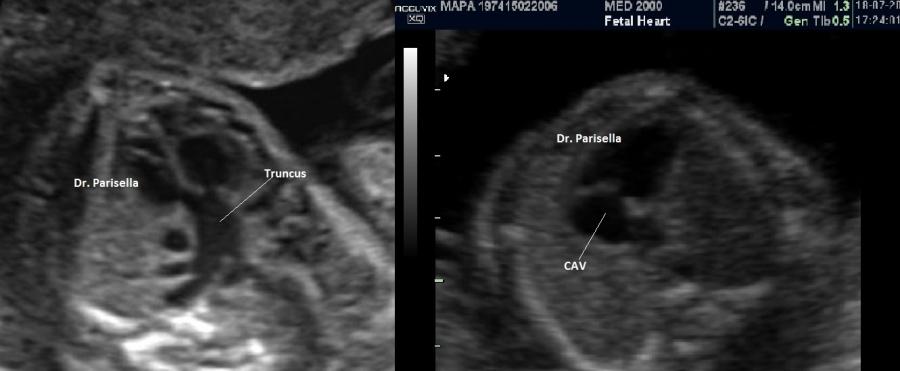

I dismorfismi facciali caratteristici sono l'ipoplasia bilaterale delle ossa zigomatiche e della mandibola (micro-

retrognazia); il palato è ogivale; sono presenti anomalie dell'orecchio esterno (anche anotia o microtia);

incostante è la presenza di anomalie della colonna vertebrale, cardiopatie congenite.

La diagnosi ecografica, difficile, si basa su:

• micro-retrognazia

• anomalie orecchio esterno

• palatoschisi

• anomalie della colonna vertebrale

• cardiopatie congenite